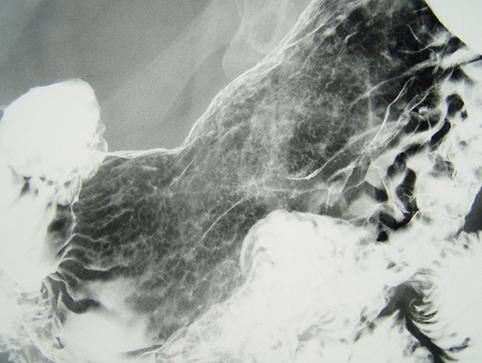

clasificación del pacienteTumor Epitelial Maligno/Adenocarcinoma

parte(separada por órganos)estómago(región)/ángulo

método de exámenRayos X

clasificación ectoscópica de tumoresTipo 0(tipo superficial)/Tipo IIc(IIc)

diámetro mayor del tumor30 - 34

grado de penetraciónm